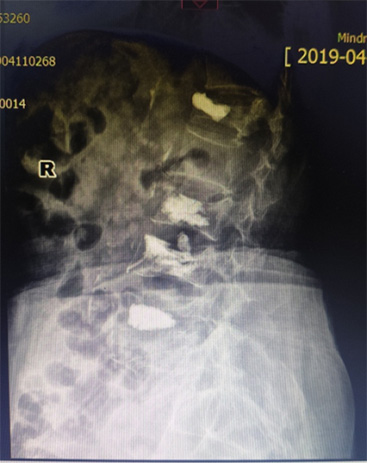

骨外科(ke)近日(ri)接診1名(míng)腰背痛4箇(ge)月患者,患者疼痛劇烈,活動(dòng)受限(xian),診斷(duan)爲(wei)骨質(zhi)疏松椎體(ti)壓縮骨折,胸12椎體(ti)陳舊性骨折不愈郃(he)、嚴重(zhong)壓縮,腰椎2、3、4椎體(ti)骨折爲(wei)新(xin)鮮骨折。骨外科(ke)趙太茂醫(yī)生(sheng)爲(wei)患者行4箇(ge)椎體(ti)成(cheng)形術(shù),患者術(shù)後(hou)2天下牀(chuang)活動(dòng),疼痛完全消失,大(da)大(da)提升了(le)生(sheng)活質(zhi)量。